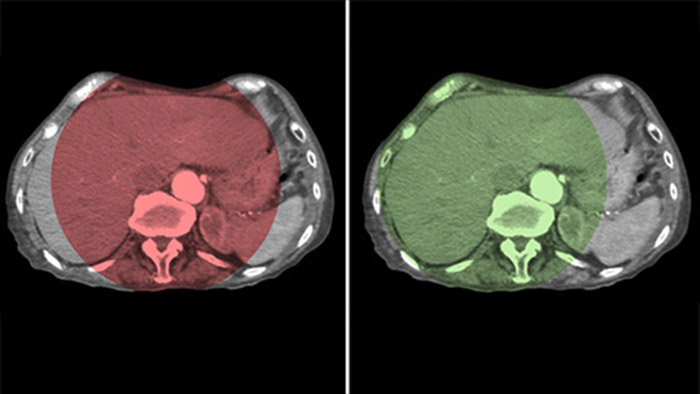

Fusion d’images avec double affichage

Le double affichage permet la visualisation simultanée de deux ensembles de données CBCT. La phase artérielle et la phase retardée s’affichent l’une à côté de l’autre ou dans une seule vue fusionnée superposée.